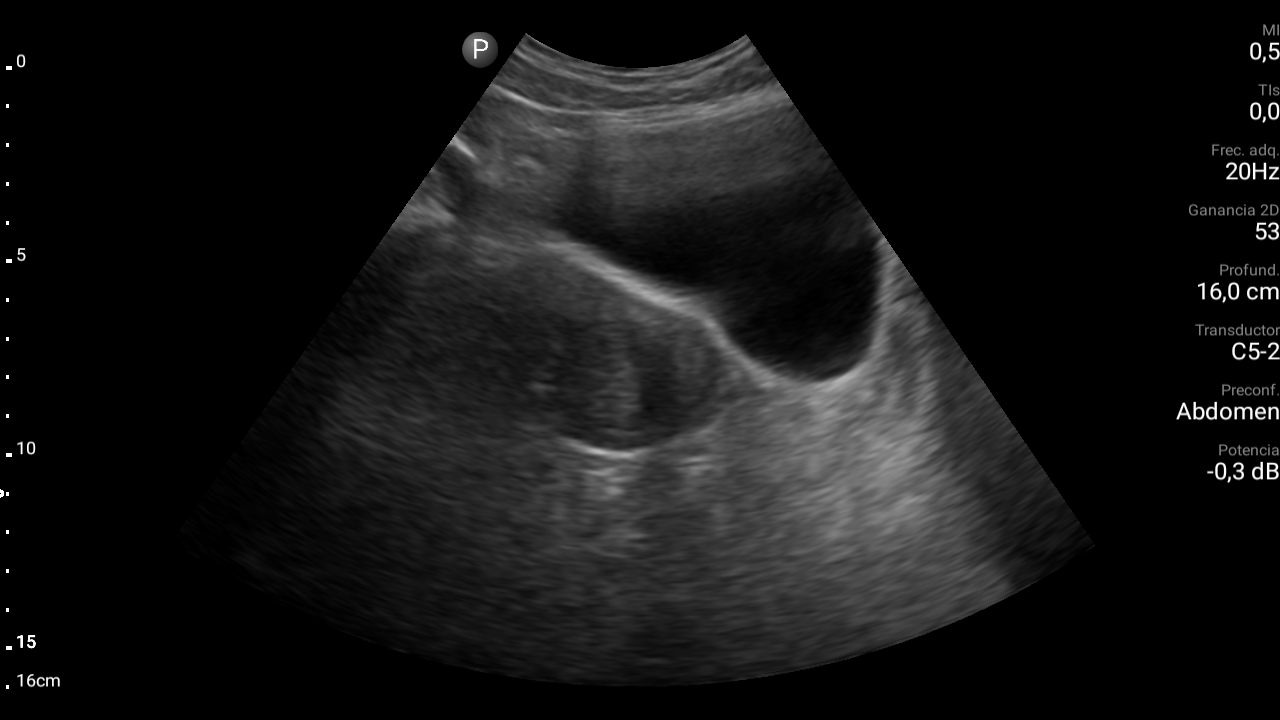

Ecografía abdominal: se observa masa hipoecoica dependiente de útero por lo que se remite de forma preferente a ginecología.

Diagnóstico: mioma uterino.El diagnóstico diferencial habría que realizarlo entre adenomitosis (ausencia de cápsula que separa la formación del tejido miometrial normal), sarcoma, leiomiosarcoma (tumor maligno), salpingitis, endometriosis, embarazo ectópico, torsión ovárica, rotura de ovario, patología urológica (cólico nefrítico…) o patología digestiva (enfermedad inflamatoria intestinal, pseudoobstrucción intestinal…).